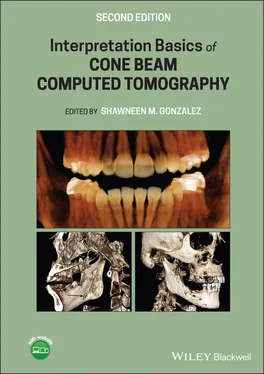

Figure 1.1. (a) 3D rendering of a small FOV of 5 cm × 8 cm from an anteroposterior (AP) view. (b) 3D rendering of a small FOV of 5 cm × 8 cm from a lateral view.